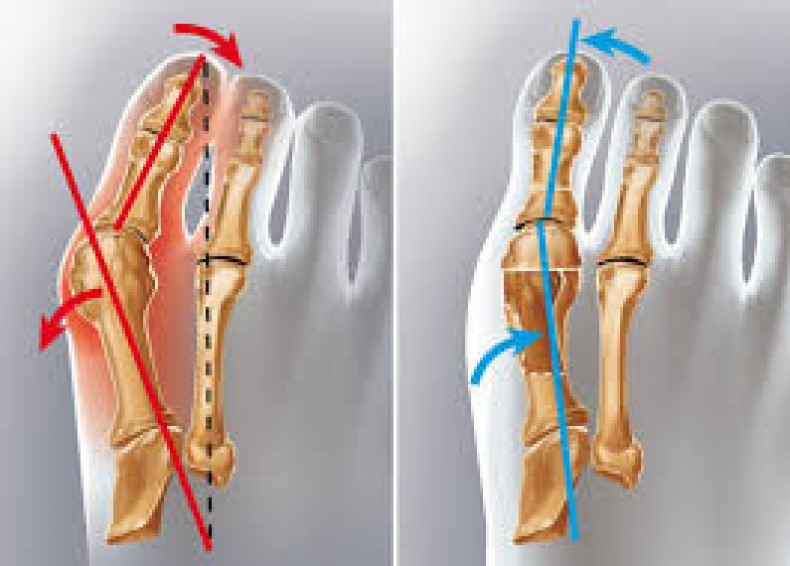

Шишка на нозі, бурсит або вальгусна деформація першого пальця – найчастіша патологія стопи. Розвивається внаслідок відхилення великого пальця у бік інших, що супроводжується травматизацією суглоба. У відповідь на травму на ньому утворюється кістковий нарі

• Викривлення великого пальця, зміна його положення стосовно анатомічної осі та інших пальців стопи.

• Причини: Компесаторне вкорочення мяза. який відповідає за розгинання великого пальця ноги.